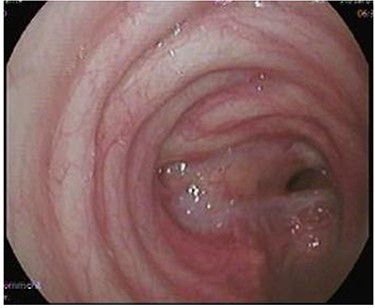

Case 3—tracheal injury

A 29-year-old male presented to the Trauma Unit, after being hit by a car. Because of desaturation, diminished air entry bilaterally and subcutaneous emphysema, he was intubated, and bilateral chest tubes were placed. After stabilization, a pan-CT scan revealed extensive soft tissue emphysema in the neck and chest, as well as pneumomediastinum. An additional two chest tubes were placed bilaterally because of incomplete lung expansion (Fig. 1). The patient improved over several days and was eventually discharged home in stable condition.

After discharge, the patient presented to the Emergency Room with shortness of breath and tachypnea. Chest X-rays and CT scan were unremarkable; however, he was admitted with type 2 respiratory failure and placed on noninvasive ventilation. Due to persistent tachypnea, the patient’s initial CT scans were reassessed with reconstruction and showed a complete transection of the trachea that was overlooked initially (Fig. 2). Flexible bronchoscopy revealed a significant post-traumatic tracheal stenosis (Fig. 3). It was tight stenosis (2 cm length on the CT reconstruction) and just above the carina. The patient was taken to the OT, with the ECMO team on standby. During rigid bronchoscopy, the patient became more hypoxic, and VV-ECMO was instituted. The stenosis was dilated with a small (#6) endotracheal tube (ETT) placed across the stenosis. He subsequently returned to the OT for further dilation and placement of a # 7.5 ETT. After 9 days, bronchoscopy revealed no gross residual stenosis and therefore the patient was successfully extubated. The patient was removed from ECMO support on the following day. After several days, the patient developed tachypnea, tachycardia and a respiratory acidosis. He was reintubated and shifted to the OT again (with ECMO standby) for redilation of restenosis with a #8 ETT in place. A covered tracheal stent was placed intraoperatively via rigid bronchoscopy (Fig. 4 A–C). Later on, the patient was extubated and eventually discharged home in stable condition.

(A) Rigid bronchoscopy show 4 mm stenosis of the distal trachea, (B) intra-tracheal showing the stent following dilatation and placement of stent, (C) plain X-ray showing stent in place, feeding tube and endotracheal tube.